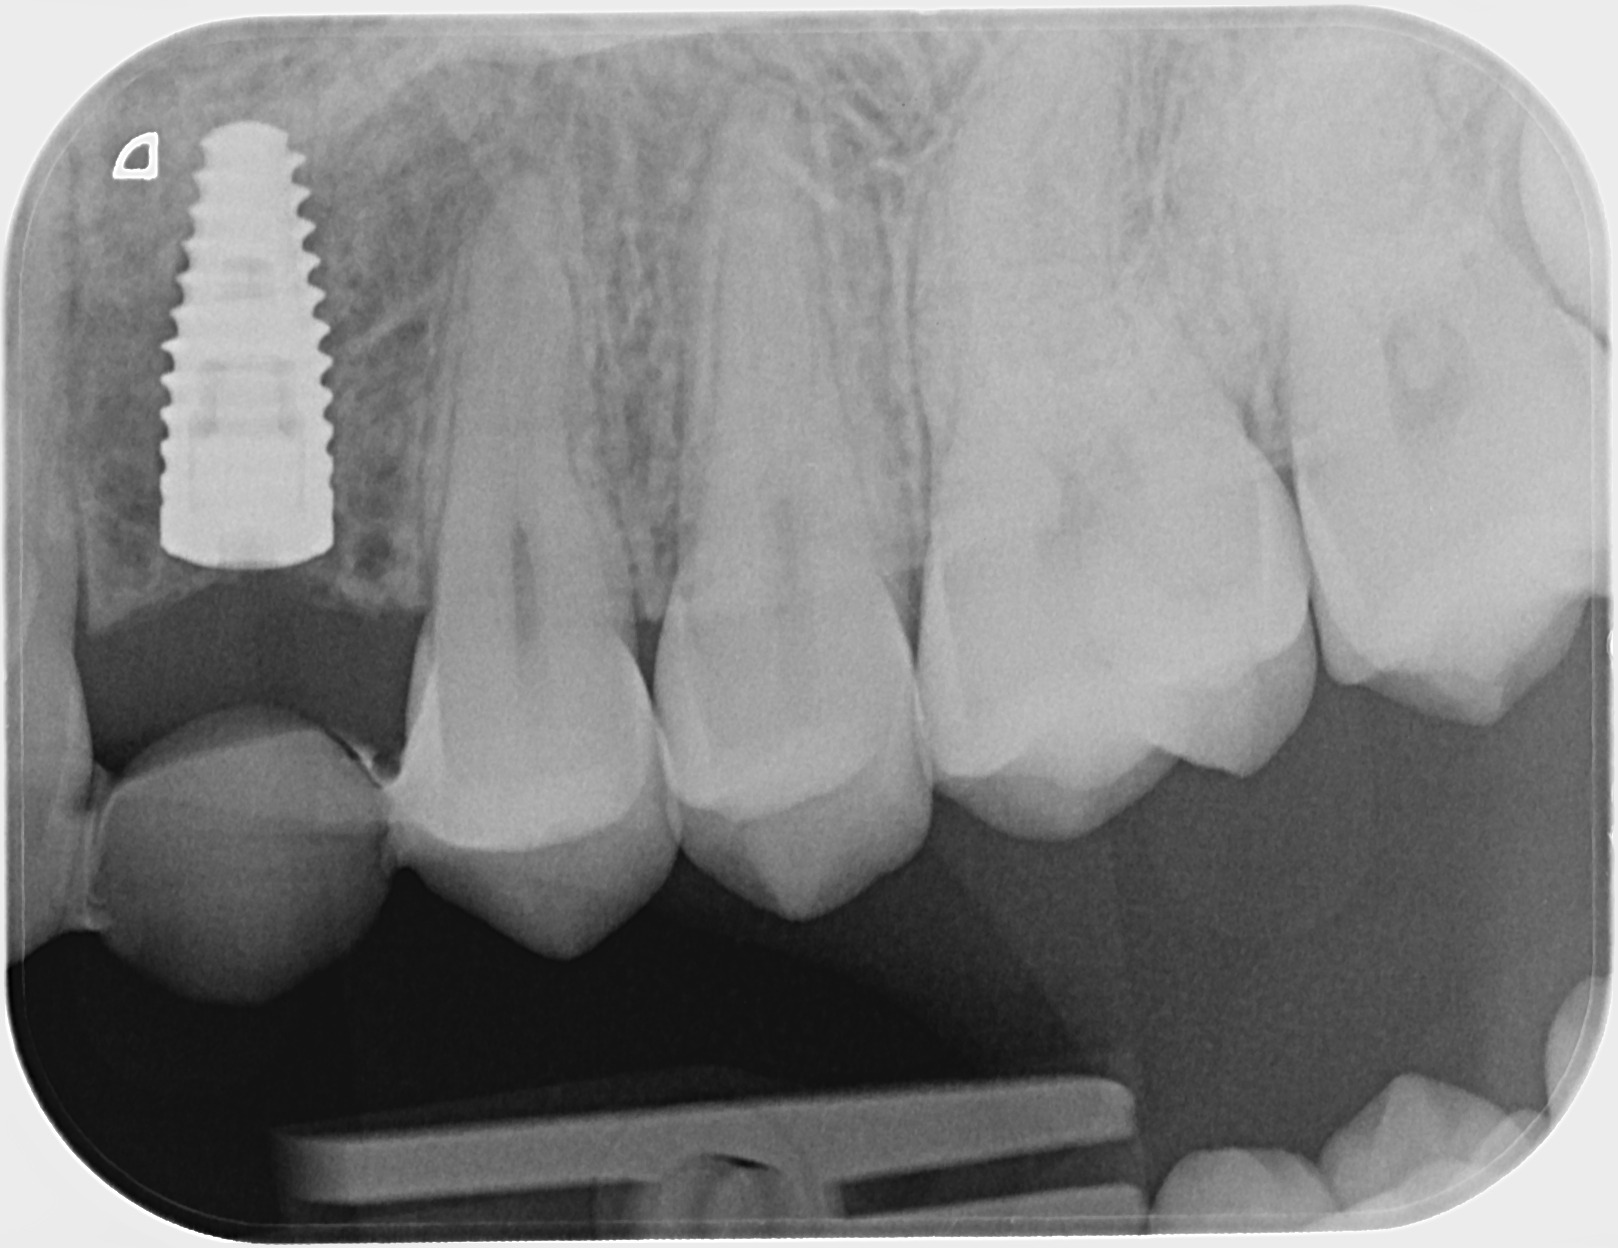

Implantti asetettu paikoilleen. Kevytsilta kiinnitetty takaisin paikoilleen väliaikaiseksi ratkaisuksi.

Alkutilanne ennen kevytsiltaa. Kulmahammas poikittain syvällä luun sisällä, maitohammas pysyvän kulmahampaan paikalla. Hoidon aikana molemmat poistettu. Ja implantti asetettu paikoilleen